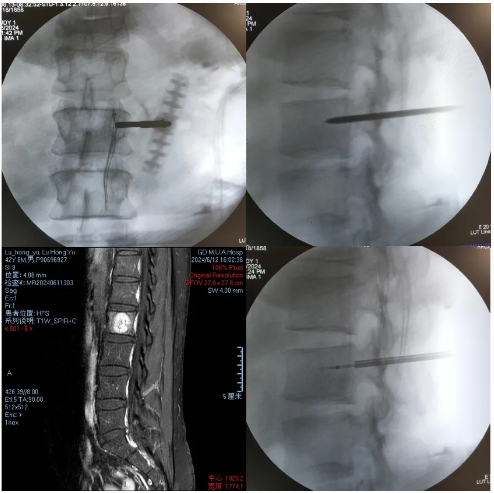

·患者陆某某,男,42岁,因反复腰背部疼痛1年余入院。腰背痛VAS评分6分。

·诊断:腰2椎体痛性血管瘤

首例局麻下智能控温射频消融治疗椎体痛性血管瘤

患者手术全程保持清醒,射频消融过程中无任何不适。术后第一天佩戴腰围起床活动。术后腰背痛VAS评分3分。